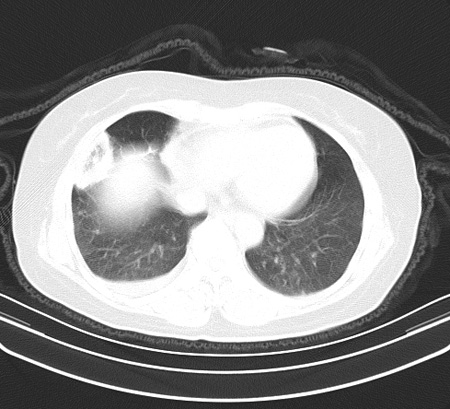

以下是引用余辉在2009-2-19 20:10:00的发言:[br]多考虑急性感染性病变,右中叶尚可见多枚小斑片状影,多为化脓性肺炎,双侧胸腔积液

以下是引用随光逐影在2009-2-19 20:33:00的发言:[br]1)考虑右肺炎症;建议抗炎治疗后复查。2)双侧胸腔积液(以右侧为甚)。

以下是引用花凤凰在2009-2-19 20:46:00的发言:[br]病人有发热,胸痛急性起病,主要病变位于右肺中叶外侧段,呈楔行改变,位于外带胸膜下,考虑为肺梗塞可能!!!!!!!!!!!!!!!!!!!!!!!!!!!!!!!!!!!